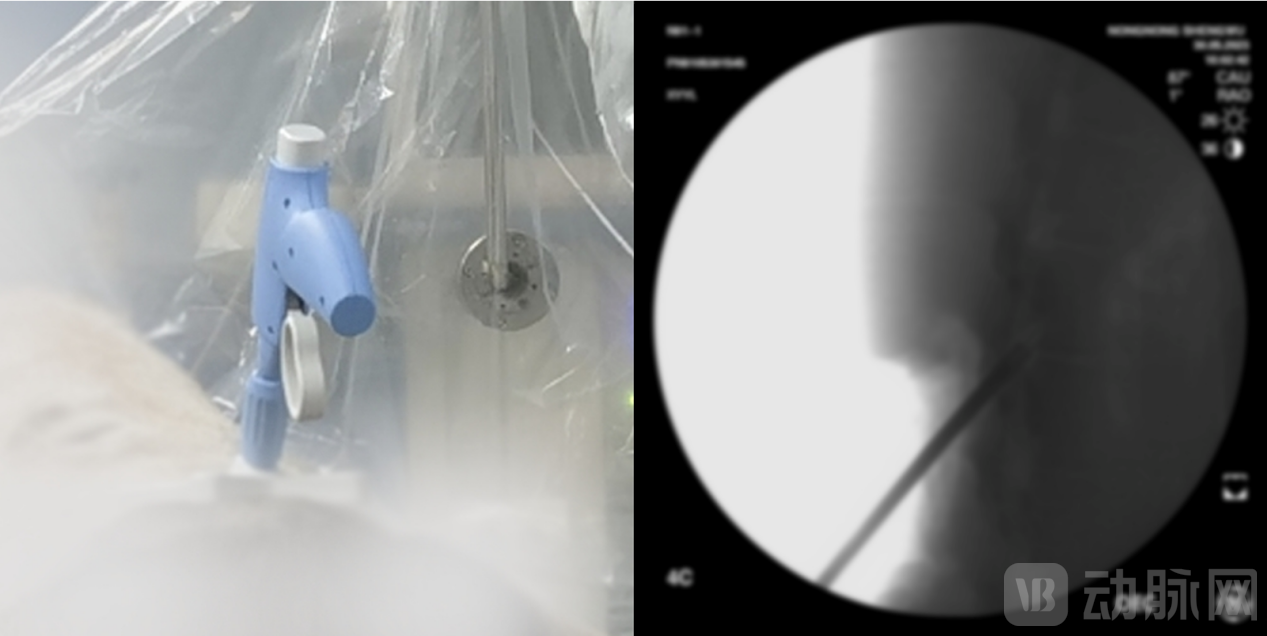

在覆盖疼痛患者多、手术量大的微创介入领域,新云医疗自主研发出国内首款针对腰椎管狭窄症(LSS)的微创手术器械套件NewMild,将为黄韧带肥厚型LSS提供更优术式。该微创手术仅需一个微小的切口即可切除多余韧带,从源头上治疗LSS,且具有类似于硬膜外类固醇注射的安全特性,患者通常在手术24小时后便可自由活动,在缩短患者康复期的同时也减轻其经济负担。

利用NewMild开展腰椎管狭窄症微创减压手术

腰椎管狭窄患者广泛分布在基层,通过NewMild开展手术,可降低操作难度,缩短基层医生学习曲线,提高基层患者的治疗率。赵云提到,在患者自愿且条件允许的情况下,这类腰椎管狭窄症微创术式有望开展日间手术,缓解医院床位紧张的问题,整体的手术费用也会降低。